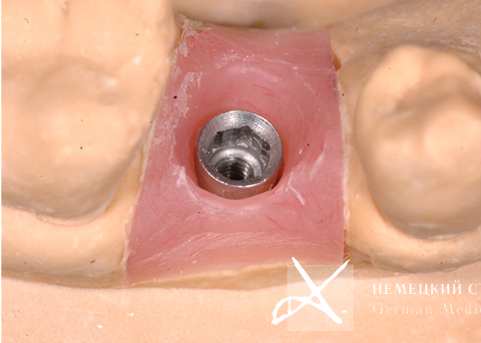

Учитывая тот факт, что диаметр имплантата практически всегда вынужденно меньше диаметра восстанавливаемого зуба в данной анатомической области, чтобы получить максимально эстетический и функциональный результат, было сделано:

- Поэтапное "выстраивание" десневого контура ("кратера прорезывания") с помощью индивидуально моделируемой диагностической промежуточной коронки и индивидуально построенной супраструктуры (абатмента), выполненной из золотосодержащего сплава.